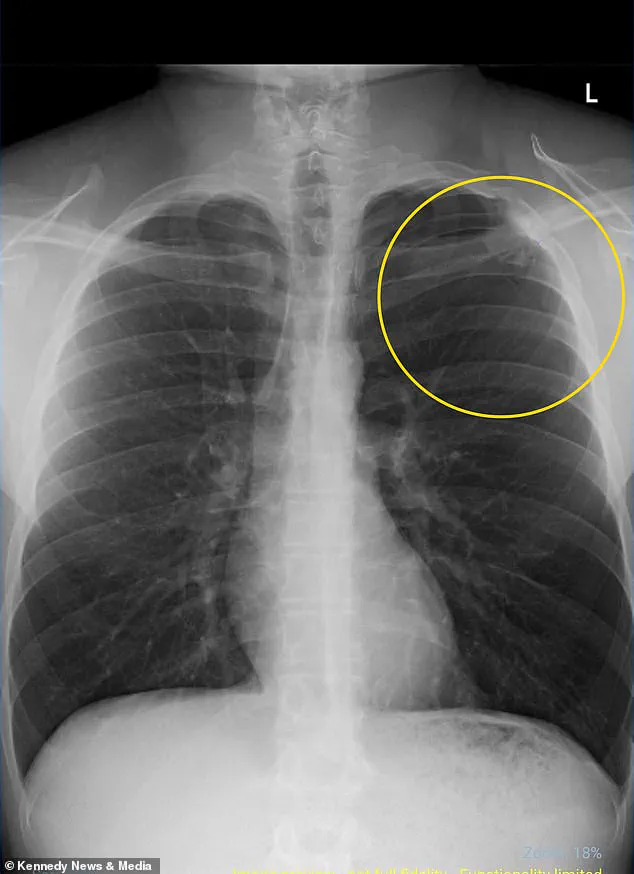

Rushed to the hospital, doctors diagnosed him with a collapsed lung, a condition known as a pneumothorax.

This occurs when air leaks into the chest cavity, creating pressure that forces the lung to partially or fully collapse.

His lung had collapsed by only 10 percent, classified as a minor collapse, and he made a full recovery with pain medication, supplemental oxygen, and an overnight hospital stay.